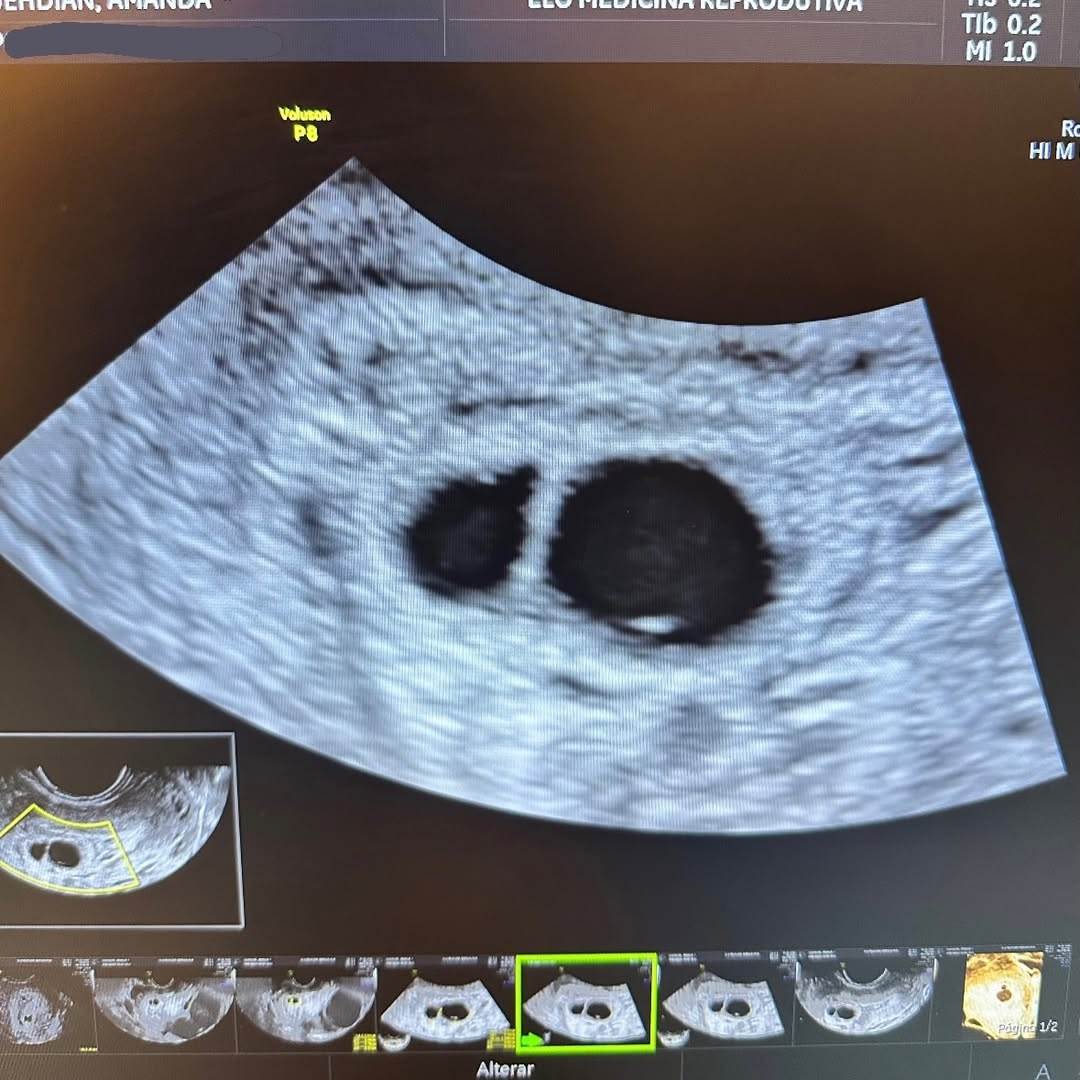

Amanda Djehdian usou as redes sociais neste domingo, 8, Dia Internacional da Mulher, para compartilhar um relato sobre um novo momento extremamente difícil em sua vida. A ex-BBB contou aos seguidores que sofreu mais uma perda gestacional, desta vez enquanto esperava gêmeos.

Infelizmente, um ano depois de perder nosso primeiro bebê, nós novamente sofremos a perda de não um, mas dois bebês lindos", escreveu.